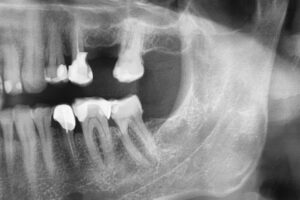

| Radiografia digitală retroalveolară | Radiografia cefalometrică – teleradiografia |

| Radiografia digitală panoramică (opt) | Tomografia Computerizată CBCT – CT 3D |